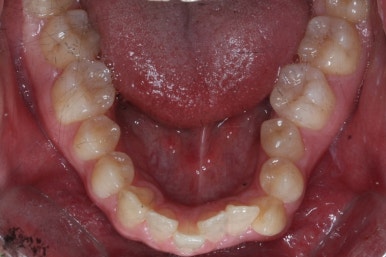

부산구순구개열 키다리아저씨치과에 처음 오셨을 때의 입 안의 모습입니다.

입천장이 갈라져서 어릴 때 봉합 수술을 했기 때문에 그 상처가 굵게 남아있는 것을 볼 수 있습니다. 일반적으로 피부상처도 다른 부위보다 단단하듯이 입천장의 봉합 상처도 매우 단단하게 아물기 때문에 성장에 방해를 주게 됩니다.

가로폭이 매우 좁고 찌그러져 있습니다.

또한 위턱이 앞으로 자라나는 것도 방해해 대부분 앞니가 거꾸로 물리게 됩니다.

또한 가랄져 있던 선에 걸쳐 있는 영구치 일부는 선천결손이 되는 경우가 많습니다.

이번 환자분도 이런 특징을 모두 갖고 계셨습니다.